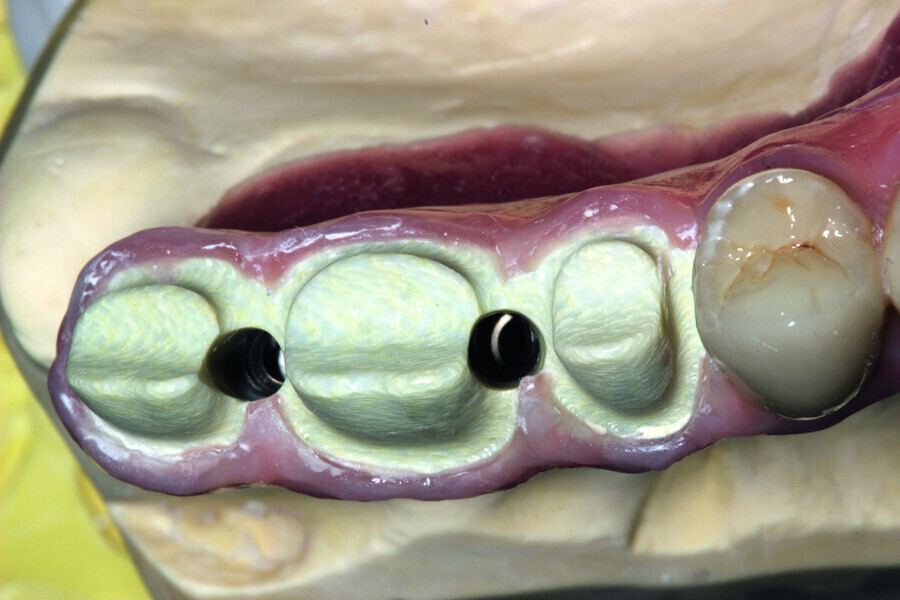

Fig. 12: Test of the construction within the oral cavity—visible opening for screws.